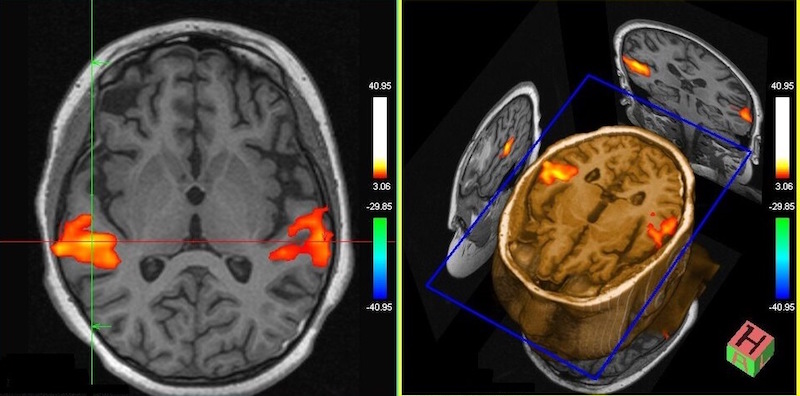

El Instituto Biomédico Quaes es actualmente el primero y único en España en contar con este equipamiento. Los estudiantes trabajarán sobre imágenes de casos, tanto de resonancia magnética como de tomografía computarizada, como procedieran de pacientes reales, y optimizarán todos los parámetros técnicos como realizaran las exploraciones requeridas en una clínica u hospital.

Gracias a los simuladores oficiales de Siemens Healthineers, los alumnos aprenderán a planificar estudios de resonancia magnética de las diferentes zonas del cuerpo; a entender cuáles son los parámetros necesarios para obtener imágenes óptimas, 以便, 之后, el facultativo pueda llevar a cabo un diagnóstico exacto, así como a observar las patologías más frecuentes, todo ello en un entorno seguro.